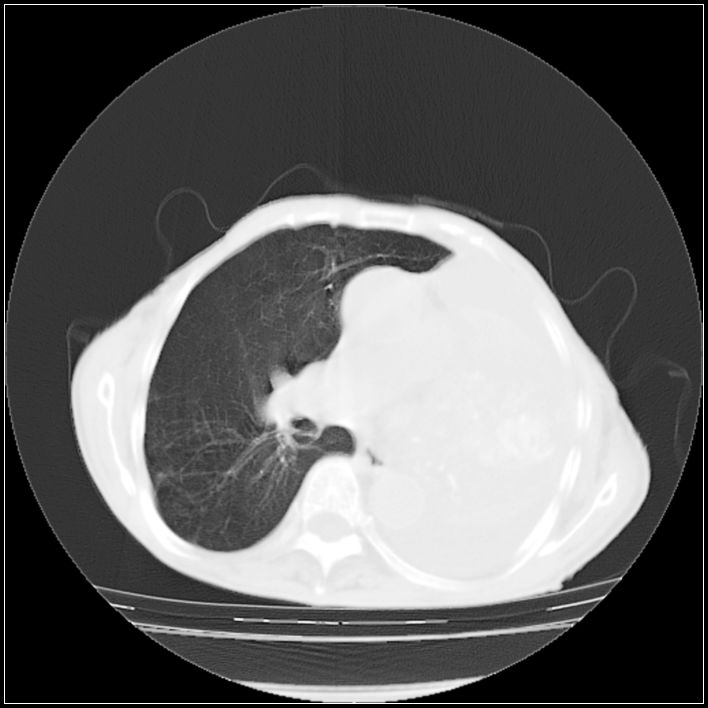

以下是引用ydx_74在2008-5-31 16:08:00的发言:[br]中心性肺癌并左侧肺不张、胸水。

以下是引用影象小辈在2008-5-31 16:25:00的发言:[br]左侧胸腔团状不规则致密影,界欠规整,密度不均匀,其内可见更低密度影及高密度影,并可见包裹性胸腔积液 考虑为1.畸胎瘤 2.肺癌